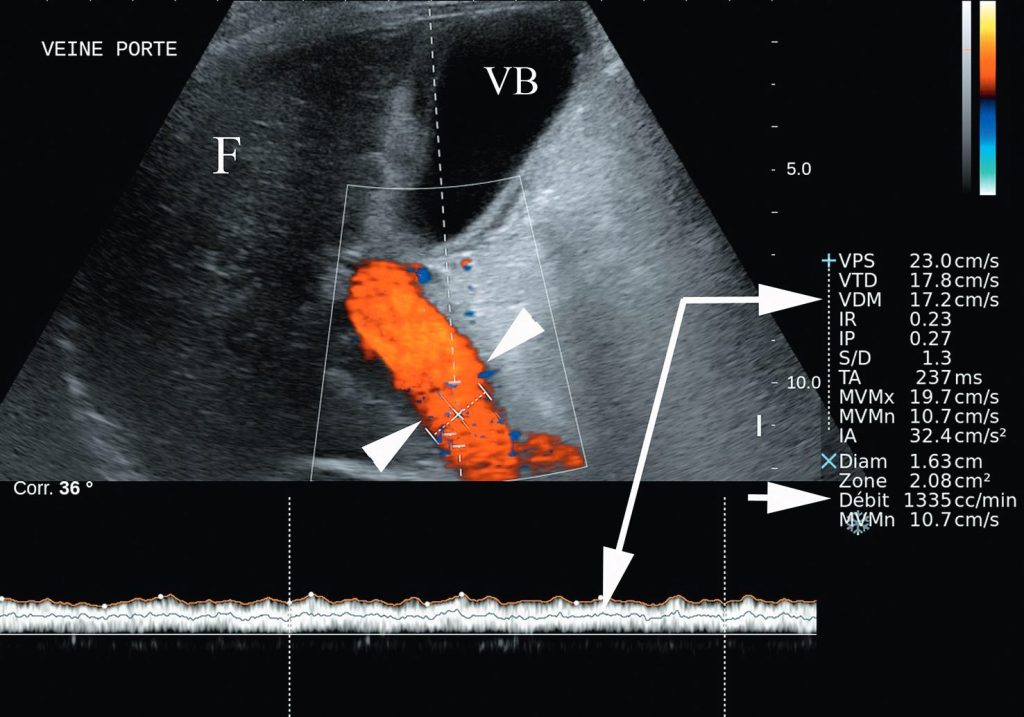

La résistance au passage du flux porte à travers le foie entraîne :

- une augmentation du diamètre du tronc porte :

- supérieure à 13 mm ;

- ainsi qu’une diminution des vitesses portales (mesurées à l’échographie-doppler) ;

- voire, à un stade évolué, une inversion du flux portal (figure 5.3).

Fig. 5.3 Exemple d’étude écho-doppler de la veine porte d’un foie de cirrhose.

La veine porte (têtes de flèche) présente un flux se dirigeant vers la sonde (codé en rouge orangé au doppler couleur) donc se dirigeant normalement vers le foie (F). On dit qu’il est hépatopète. Le doppler pulsé renseigne sur la vitesse du flux porte (ici 17 cm/s) (flèches longues). Après mesure du diamètre de la veine porte, l’échographe calcule la vitesse du flux sanguin portal (après correction de l’angle de tir) (flèche courte). En cas d’hypertension portale, la vitesse diminue, le flux porte peut même s’inverser et devenir hépatofuge. Des veines de dérivation peuvent être visibles en doppler couleur, mais elles sont plus facilement détectées au scanner.

Source : CERF, CNEBMN, 2022.